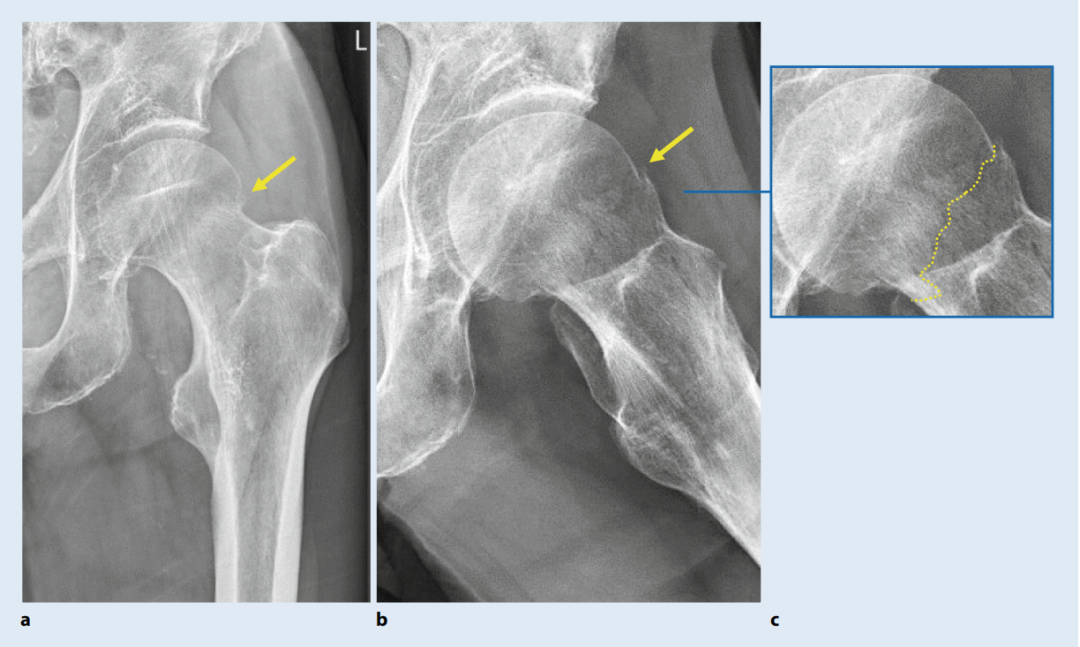

图1. a 显示了股骨颈骨折的不同形式及其与其他股骨近端骨折类型的区别,图 1b 显示了供应髋关节的血管位置(图 1a, b)。

图3. A 典型无移位Garden I型股骨颈骨折(SHF)左髋关节两个平面的X线片。髋关节在X线片上未见明显骨关节炎征象。患者在跌倒事件前生活自理且活动自如。在这种情况下,接骨术是适应证,目标是长期保留髋关节。a 在前后位投照中,皮质中断几乎无法辨认。注意此处有一个高密度区域,提示骨性嵌插或投影相关的轻微股骨头倾斜。b 在Lauenstein位片中,可以清晰地看到骨折线伴轻微台阶,在放大图(c)中示意性描绘(虚线)。箭头指向延伸至皮质的骨折线。